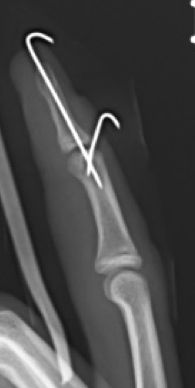

Se trata de una deformidad del dedo con flexo de la falange distal por lesión del tendón extensor o un arrancamiento óseo en la base de la tercera falange. Es más frecuente en la adolescencia, aunque puede ocurrir a cualquier edad. El dedo en martillo tendinoso por rotura del extensor sin lesión ósea se trata con una férula con la IFD en extensión durante 8 semanas. Se debe realizar un tratamiento quirúrgico cuando existe fractura con un fragmento avulsionado superior al 40% de la superficie articular pudiendo realizar diferentes técnicas quirúrgicas. (Figura 19)

Figura 19: a, b- Fractura de la falange distal desplazada con avulsión tendón extensor. Tratamiento quirúrgico mediante técnica de Ishiguro